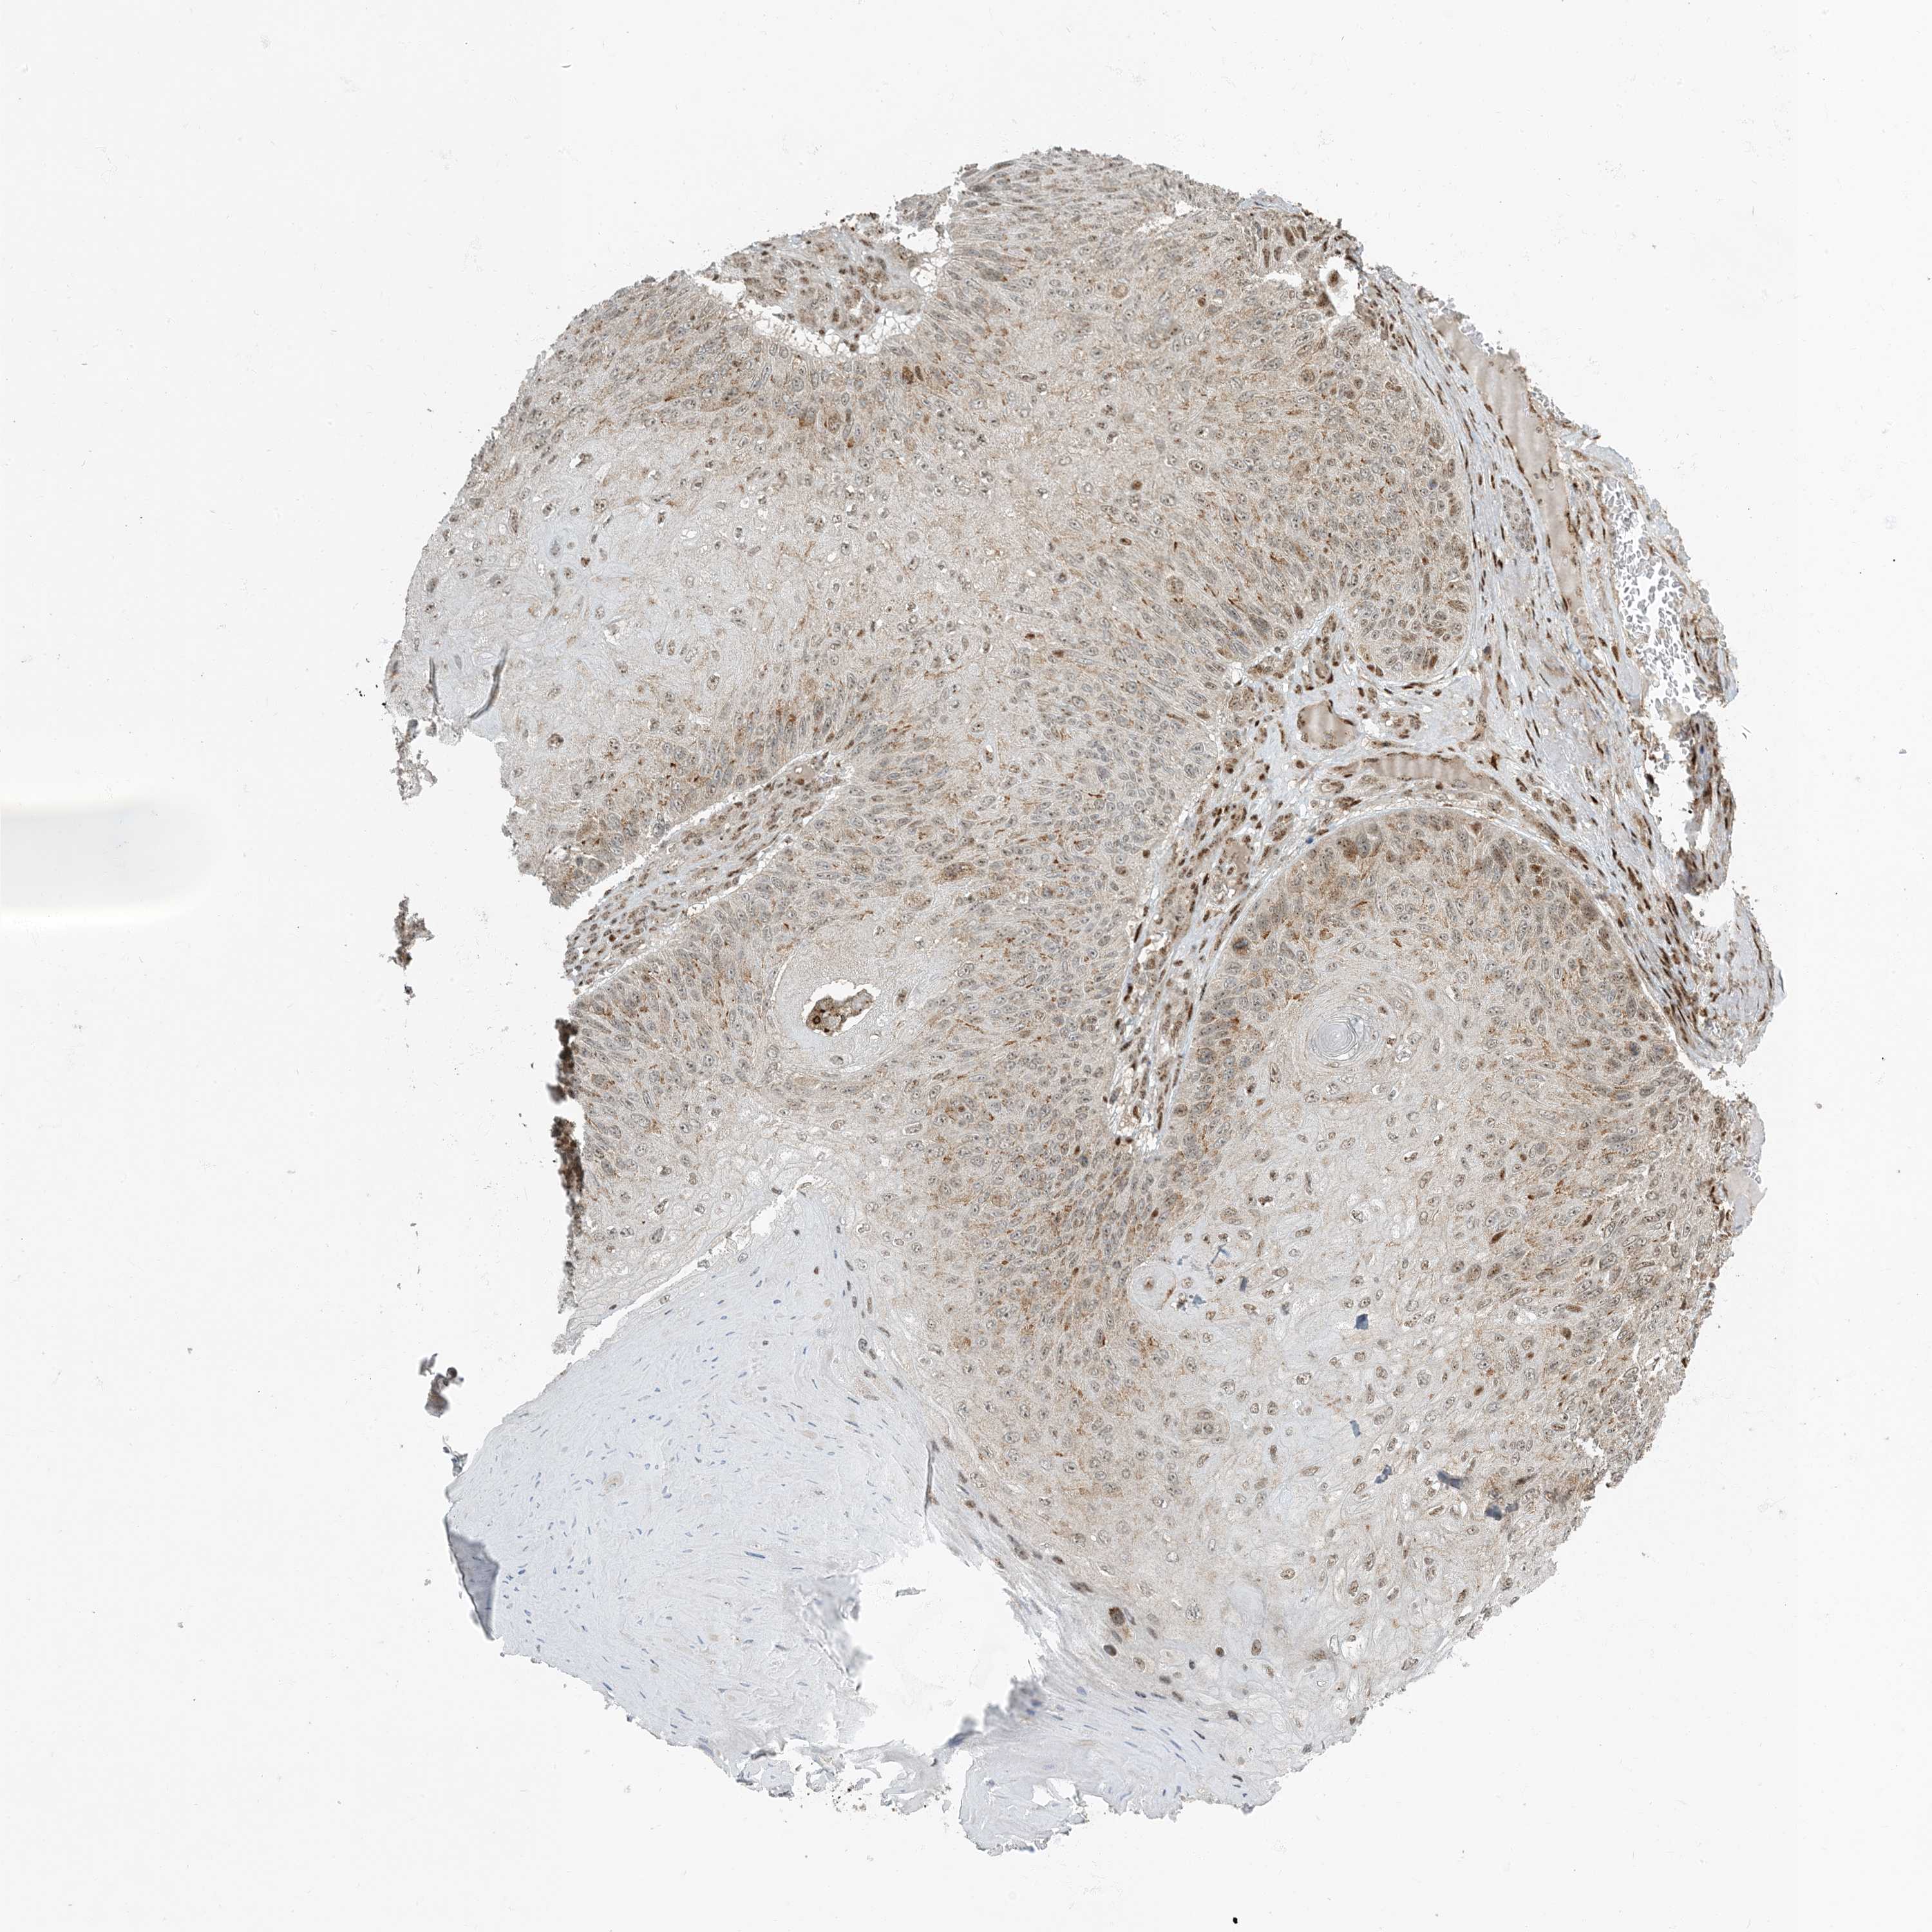

SKIN CANCER - Protein expressioni

A mouse-over function shows sample information and annotation data. Click on an image to view it in a full screen mode. Samples can be filtered based on level of antibody staining by selecting one or several of the following categories: high, medium, low and not detected. The assay and annotation is described here.

Antibody stainingi

Antibody staining in the annotated cell types in the current human tissue is reported as not detected, low, medium, or high, based on conventional immunohistochemistry profiling in selected tissues. This score is based on the combination of the staining intensity and fraction of stained cells.

Each image is clickable and will lead to virtual microscopy that enables deeper exploration of all samples and also displays staining intensity scores, fraction scores and subcellular localization as well as patient and tissue information for each sample.

Antibody CAB036003

Staining

High

Intensity

Strong

Quantity

>75%

Location

Nuclear

Squamous cell carcinoma in situ, NOS

Squamous cell carcinoma, NOS

Basal cell carcinoma

Adnexal tumor, benign

Squamous cell carcinoma, metastatic, NOS